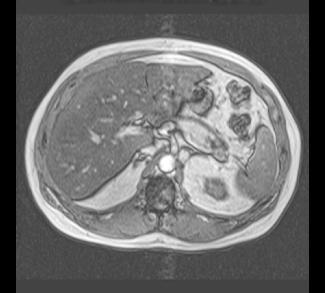

These are both MR images (note the dark appearance of bone and high signal fat). The image on the left is an in-phase image and the image on the right is an out-of-phase image, which causes a number of artifacts (a black outline around many structures, called 'India Ink' appearance) but also causes signal from fat to decrease. The liver is brighter on the in-phase than the out-of-phase image, indicating that it has diffuse fatty infiltration. MR is not used as frequently as CT overall in abdominal imaging, but can solve particular problems, such as detecting small amounts of fat within organs or lesions, which can often help in the differential diagnosis of complex cases.